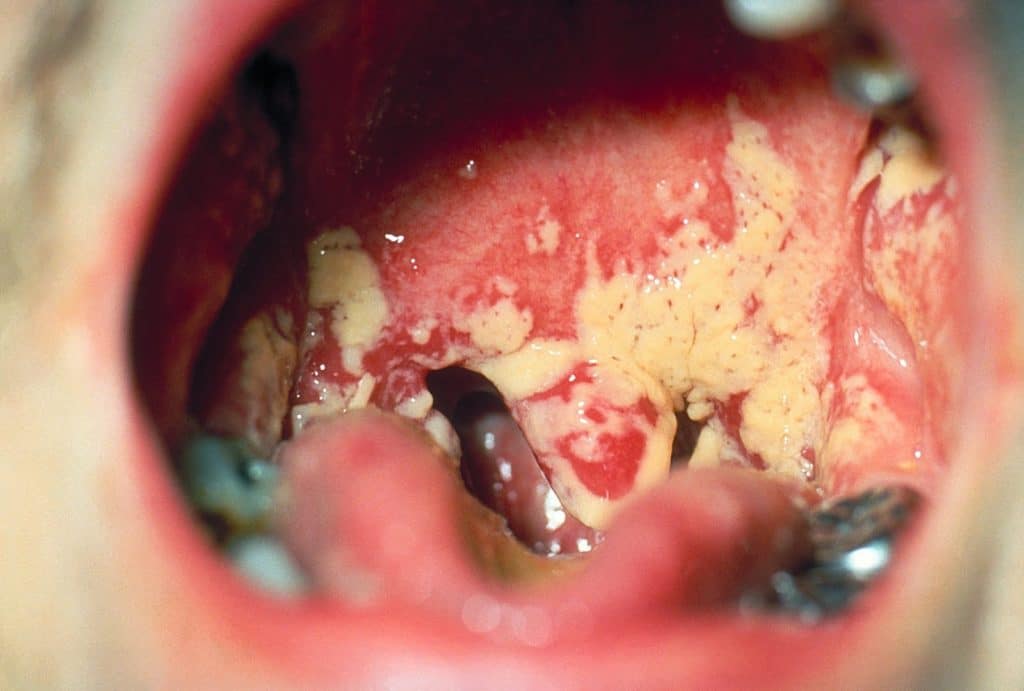

У більшості випадків винуватцем поразки виступає умовно-патогенний гриб Кандида. Грибок в горлі, особливості прояву якого можна побачити на фото з зображенням ураженої зони, провокується наступними причинами і факторами:

Слід відстежувати появу будь-якого дискомфорту в горлі. Іноді відбувається скупчення слизу, поява відчуття печіння, навіть при самостійному огляді видно наліт – це гриби Кандида в горлі. Візуально вони схожі з плівкою суфле, яку дуже складно очистити.

- Білі виділення на поверхні слизової оболонки, що нагадують за консистенцією сирну масу;

- Жовтуватий наліт на задній стінці глотки і язика;

Головним симптомом того, що в горлі знаходяться патогенні грибки, є виділення і наліт. Вони поступово накопичуються і покривають собою окремі частини носоглотки. Білі крупинки добре видно на яскраво-червоній слизовій оболонці, яка подразнена.

На мигдалинах, язиці, задній стінці глотки утворюються мікотичні вогнища, що нагадують сирнистий наліт білого, жовтуватого або сіруватого кольору. Слизова оболонка у мигдалин пошкоджується і покривається тріщинами.